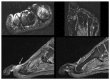

The terminology 'Morton's neuroma' may represent a simplification of the clinical condition as the problem may not be a benign tumour of the nerve, but neuropathic foot pain associated with the interdigital nerve.Foot and ankle pathomechanics leading to metatarsalgia, clinical examination and differential diagnosis of the condition and imaging of the condition, for differential diagnosis, are discussed.Nonoperative management is recommended initially. Physiotherapy, injections (local anaesthetic, steroid, alcohol), cryotherapy, radiofrequency ablation and shockwave therapy are discussed.Operative treatment is indicated after nonoperative management has failed. Neuroma excision has been reported to have good to excellent results in 80% of patients, but gastrocnemius release and osteotomies should be considered so as to address concomitant problems.Key factors in the success of surgery are correct diagnosis with recognition of all elements of the problem and optimal surgical technique. Cite this article: EFORT Open Rev 2019;4:14-24. DOI: 10.1302/2058-5241.4.180025.